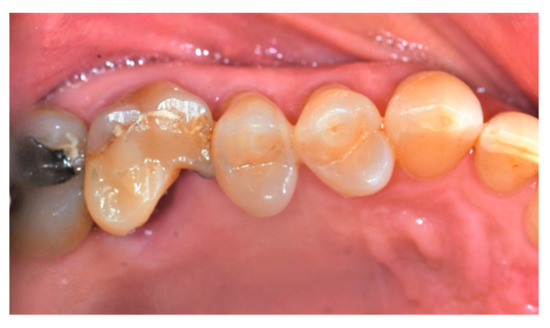

2.4. Surgical Procedure, Evaluation at Follow-Up, and Collection of Radiographic Data